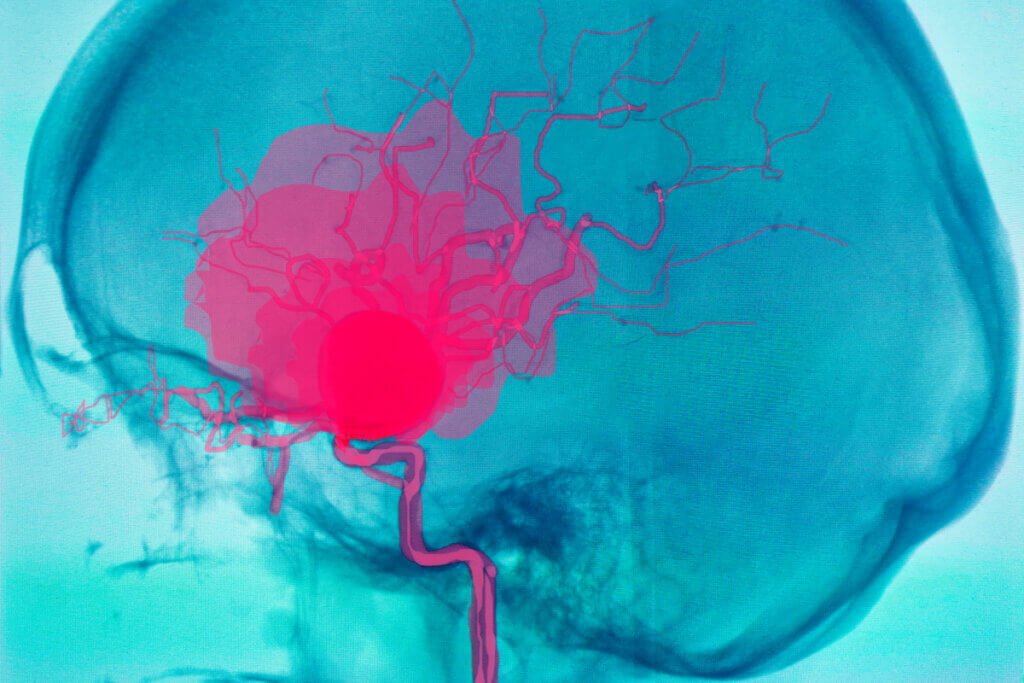

La realización de estudios imagenológicos que permitan estudiar los vasos sanguíneos es fundamental en estos casos. Una de las pruebas más utilizadas es la angiografía o arteriografía, aunque la angiotomografía y la angioresonancia también pueden ser de utilidad.

Algunos estudios recomiendan realizar una angiografía de seguimiento cada 5 años después de haber padecido un aneurisma. Esto permitirá realizar un diagnóstico precoz en caso de reincidencias.